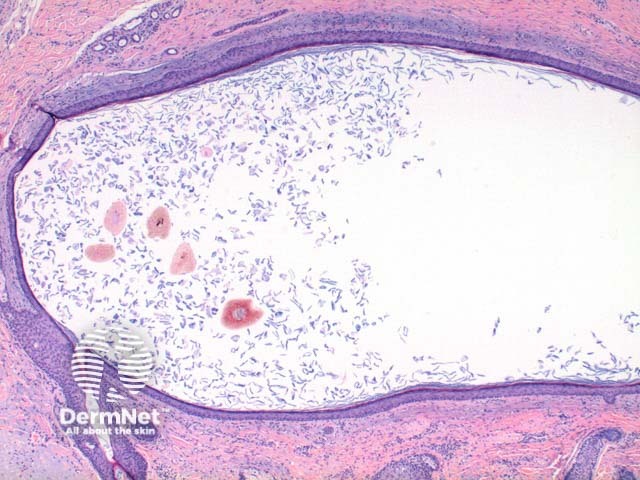

Scanning power view demonstrates a unilocular cystic structure within the dermis (Figure 1). Higher power reveals a thin epithelial lining with a retained granular layer (Figures 2 and 3). Within the cyst cavity are loose keratin fragments and numerous pigmented terminal hair shafts (Figures 2 and 3).

Figure 1